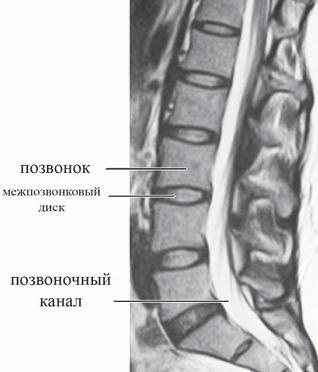

МРТ № 2

На МРТ № 2 — грудной отдел в состоянии «норма»

Грудной отдел должен иметь нормальную степень кифоза (угол кифоза по Stagnara формируется линией, параллельной замыкательным пластинкам ТIII и ТXI= 25°). Позвоночный канал на грудном уровне имеет округлую форму, что делает эпидуральное пространство узким почти по всей окружности дурального мешка (0,2–0,4 см), а на участке между TVI и ТIX он наиболее узок. Сагиттальный размер: ТI-ТХI = 13–14 мм, ТXII = 15 мм. Поперечный диаметр: > 20–21 мм.

Высота межпозвонковых дисков: самая меньшая на уровне ТI, на уровне ТVI-ТХI приблизительно 4-5 мм, наибольшая на уровне ТХI-ТХII.